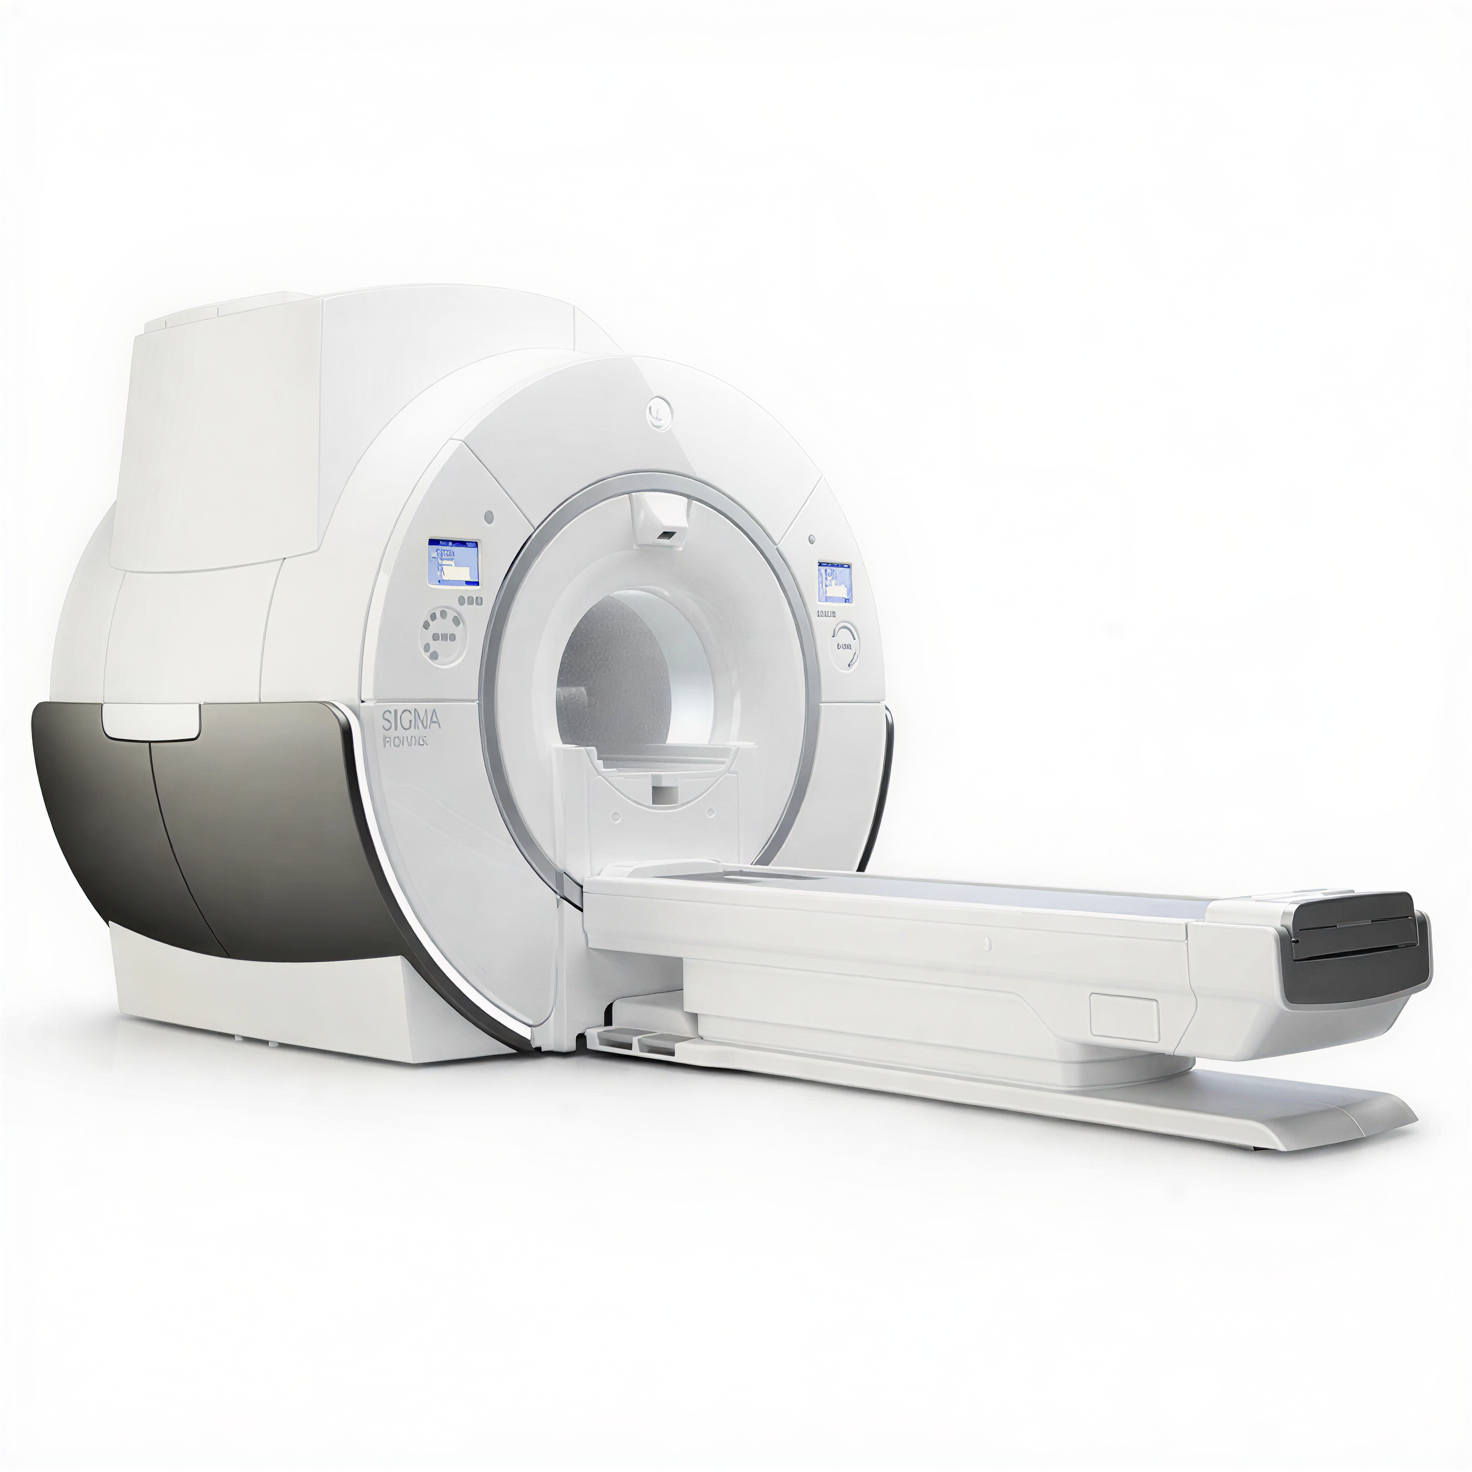

GE SIGNA Pioneer относится к актуальному поколению 3T-систем семейства SIGNA, в которых сделан акцент на сочетании высокой однородности поля, развитой градиентной системы и цифровой архитектуры приёма сигнала. Платформа проектировалась как универсальное решение для нейрорадиологии, онкологии, кардиологии, ортопедии и целотельных исследований. Широкий тоннель и комфортный стол обеспечивают удобство позиционирования пациента и снижают долю прерванных исследований, а развитые средства коррекции движения и шумопонижения (включая технологии Silent и современные алгоритмы реконструкции) помогают получать стабильные диагностические изображения даже у сложных категорий пациентов.

- Широкий тоннель и эргономичный стол пациента для повышения комфорта, снижения клаустрофобии и уверенной работы с пациентами высокой массы тела.

| Стол пациента | Комфортный моторизованный стол с продольным перемещением и низкой высотой посадки |

| Технология катушек | Совместимость с катушками AIR Technology и массивами для нейро-, body- и ортопедических протоколов |